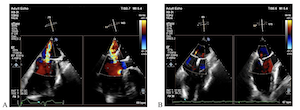

Multivalvular heart disease represents a less explored domain within cardiovascular surgery. In patients with aortic stenosis (AS) undergoing surgical or transcatheter aortic valve replacement (TAVR), the prevalence of moderate to severe mitral regurgitation (MR) ranges from 8% to 33%. Among the most common presentations are patients with severe AS and clinically significant functional MR. In instances of moderate surgical risk, open-heart surgery is typically performed, sometimes involving combined valve correction procedures. However, for patients deemed to be at high surgical risk or deemed inoperable, an interventional approach may be considered if the anatomy of both the aortic and mitral valves is conducive to such intervention. Careful analysis of each patient is essential in determining the appropriate treatment strategy, whether it involves isolated TAVR or if a staged intervention targeting the aortic and mitral valves is warranted. In the article, we present a review of the literature devoted to the strategy for bivalvular interventions in patients of high surgical risk and also a clinical case of a successful step-by-step interventional approach in an 83-year-old patient of high surgical risk with hemodynamically significant aortic and mitral valve disease, along with an analysis of the chosen approach.